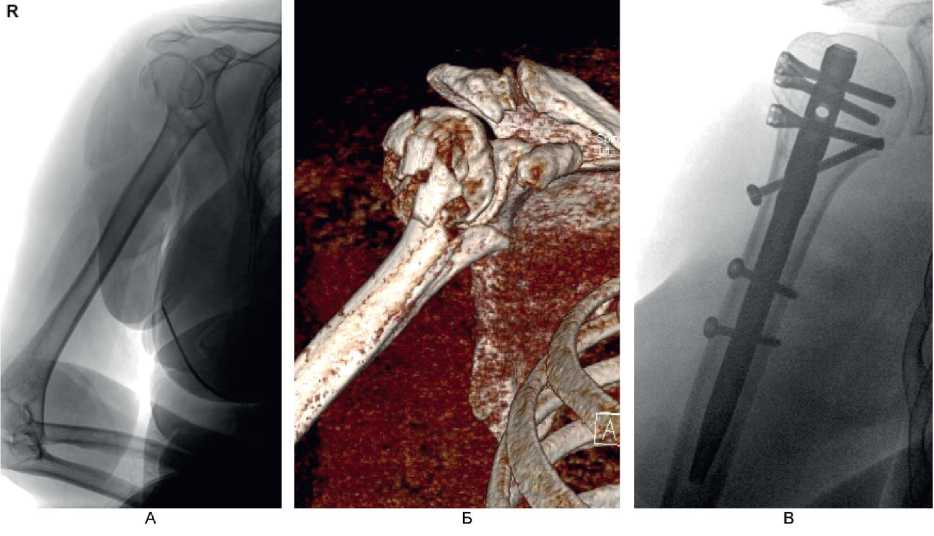

Клинический пример 2. Больной А., 50 лет, поступил в клинику ВЦЭРМ им. А.М. Никифорова в экстренном порядке. Выполнены рентгенография плечевого сустава в стандартных проекциях (рис. 8А), и компьютерная томография (см. рис. 8Б).

Рис. 8. Больной А., 50 лет. А – рентгенография плечевого сустава в стандартных проекциях; Б – компьютерная томография до операции

Перелом по классификации АО – С3.1. На 2-е сутки после поступления выполнено оперативное вмешательство – БИОС хирургической шейки правой плечевой кости. Рентгенография на 1-е сутки после операции представлена на рис. 9А, Б, контрольная рентгенография плечевого сустава через 6 мес после операции – на рис. 9В. Функциональный результат после операции – на рис. 10.

Рис. 9. Больной А., 50 лет. А, Б – рентгенография на 1-е сутки после операции; В – через 6 мес после операции